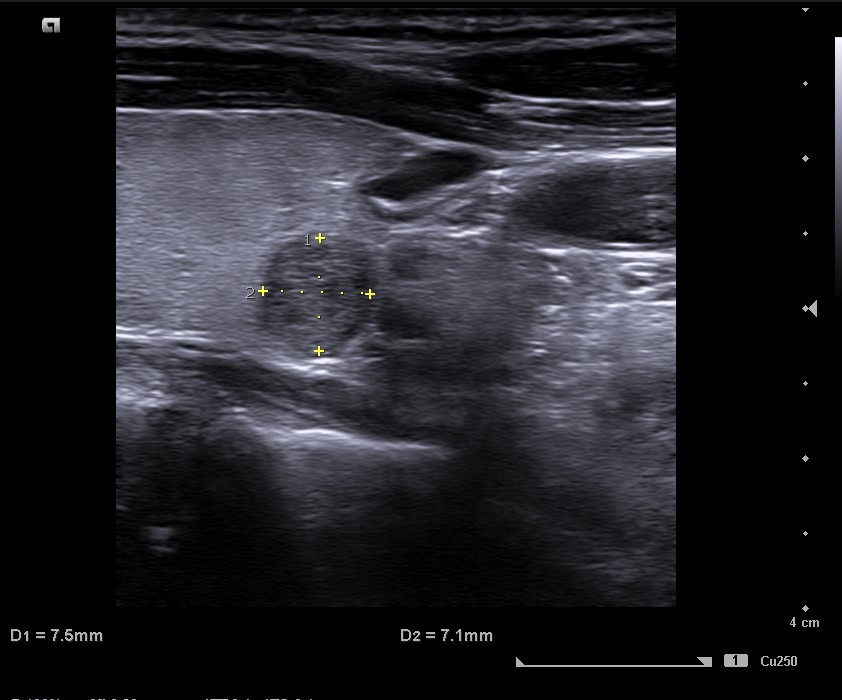

Lóbulo derecho de ecoestrucutra normal. Presenta nódulos hipoecogénicos, pero de características espongiformes y vascularización periférica en situación posteroinferior de 7,5 mm de diámetro, bien definido. TIRADS 2.